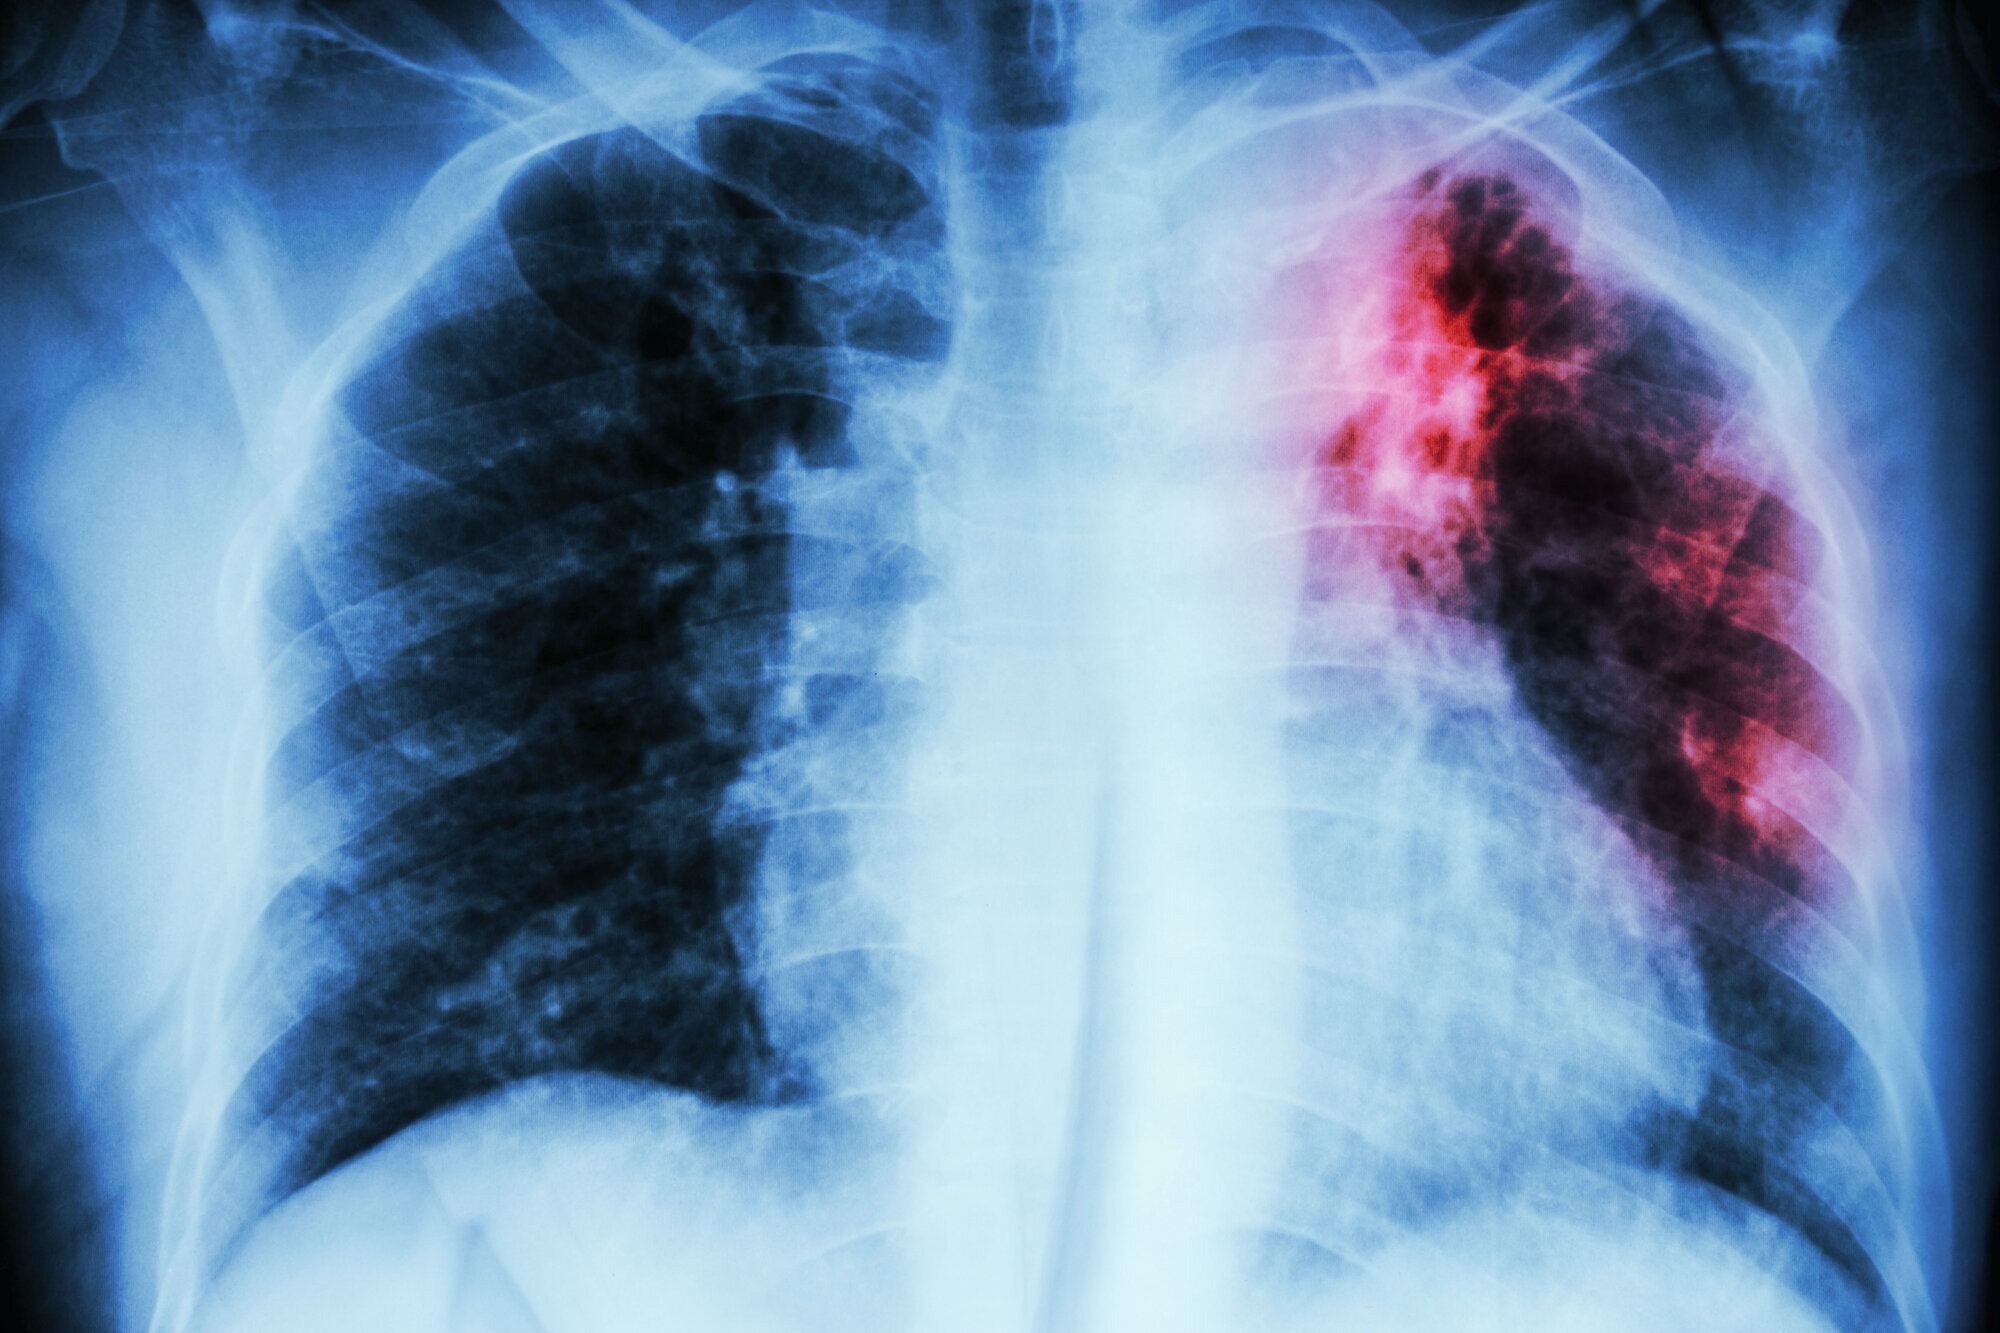

Helsepersonell med pasientkontakt har dobbelt så høy risiko for å smittes av tuberkulose som normalbefolkningen. Likevel er det ikke lenger anbefalt at de tar BCG-vaksinen.

Fra 1. juni anbefaler Folkehelseinstituttet BCG-vaksinen rutinemessig kun til to grupper av helsepersonell: De som over tre måneder skal jobbe med voksne pasienter med smittsom lungetuberkulose, eller med dyrking av mykobakterier i mikrobiologisk laboratorium.

Antallet tuberkulosesmittede i Norge gikk ned for fjerde året på rad i fjor. I 2013 fikk 392 personer tuberkulose, mens i 2017 var tallet 256. Av disse var 30 norskfødte. 16 var norskfødte med norskfødte foreldre.